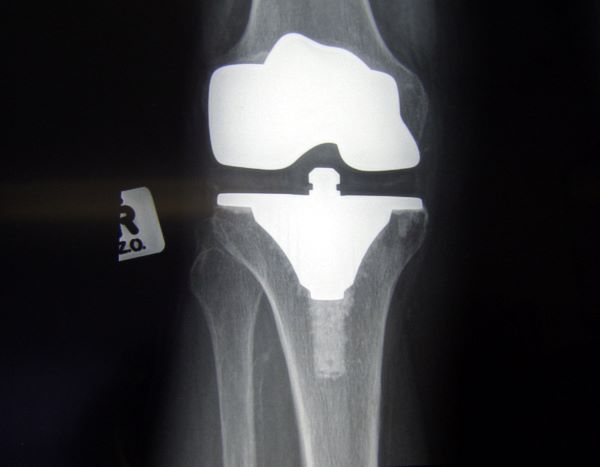

무릎 관절의 퇴행성 변화는 보행 기능에 큰 지장을 초래하며, 통증과 기능 저하가 심각할 경우 인공관절수술이 필요할 수 있다. 이 수술은 많은 환자에게 삶의 질을 회복시켜주는 효과적인 치료법이지만, 고비용 구조로 인해 진입 장벽이 높은 것도 사실이다.

인공관절수술 후 회복을 위해서는 체계적인 재활치료가 필수이다. 수술만큼이나 중요한 이 단계는 운동 범위 회복, 근력 강화, 보행 능력 정상화를 위한 중요한 과정이다.

수술 직후 약 1~2주의 입원 치료를 거친 후, 외래로 물리치료를 진행하거나 집에서 홈케어 재활을 병행하는 것이 일반적이다.